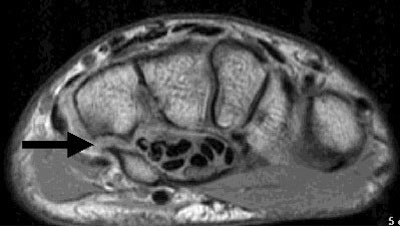

Cross-sectional imaging is frequently needed to either confirm or exclude the possibility of a fracture of the hamate. Axial T1 and/or axial proton-density MR images best display the hook of the hamate and are the preferred imaging sequences when an injury to this region is suspected.

| The axial, proton density MR image above demonstrates an oblique fracture through the base of the hook of the hamate (black arrow). The sclerosis at the margins of the picture is consistent with the clinical report of old trauma. |